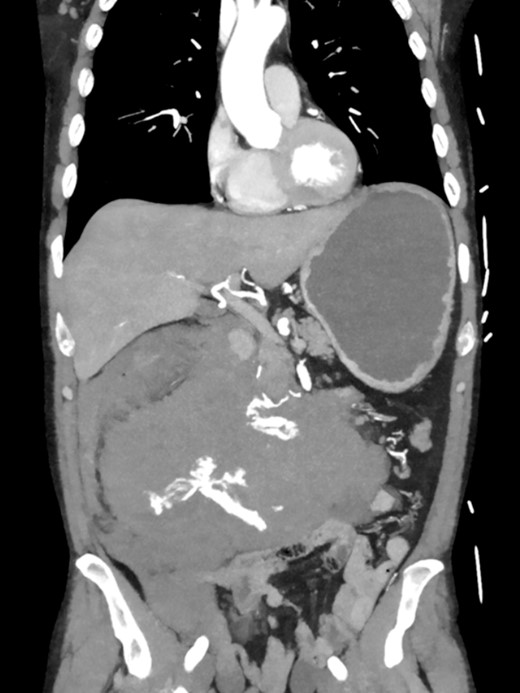

A 52-year-old otherwise healthy patient was admitted to the emergency room of our hospital with an acute abdomen and hemodynamic instability. The computed tomography (CT) angiography revealed an active, most likely aneurysmal bleeding of the pancreaticoduodenal artery with venous pooling, along with a large retroperitoneal hematoma measuring ~2000 ml in volume (Fig. 1). Due to hemodynamic instability and the unavailability of interventionalists, the decision for emergent exploratory laparotomy was made. Intraoperatively was a ballooned and hemorrhagic retroperitoneum with incipient perforation of the mesenteric root observed. To gain exposure, an extended Kocher maneuver according to Cattell–Braasch was performed, necessitating a rightsided hemicolectomy. The bleeding was managed by ligating the pancreaticoduodenal artery. An Easy-Flow drainage was placed, and a split stoma was created. Intraoperatively, due to an estimated blood loss of over 4 L, transfusion therapy was administered following a massive transfusion protocol, along with extensive coagulation correction.

CTA showing an active bleeding likely from the pancreaticocuodenal artery with venous pooling and a large retroperitoneal hematoma.